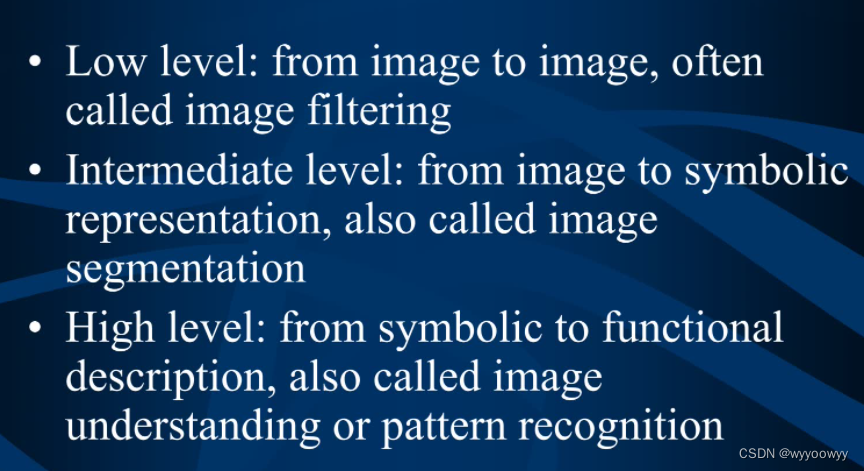

8、医学图像的处理流程

1、Low level : 图像滤波,图像的预处理

输入 : 图像,输出:图像

2、Intermediate level : 图像分割,输入:图像,输出:可能是分割后边缘的集合

3、High level :图像理解/模式识别 输入:符号集,输出:功能的表达